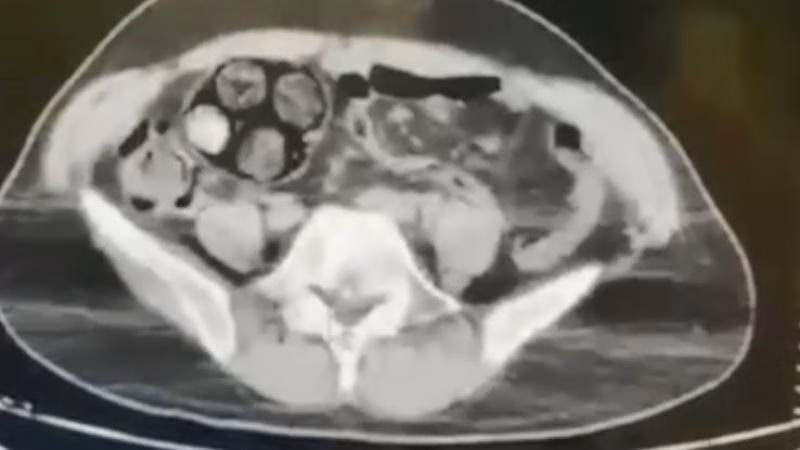

Ölümle Dans! İranlı Kuryenin Midesinden Çıkanlar Şok Etti!

Artvin’de nefes kesen bir operasyonla İranlı bir uyuşturucu kuryesinin midesinden çıkarılan paketler, sınır ötesi uyuşturucu ticaretinin vahşi yüzünü bir kez daha gözler önüne serdi. Zanlının yuttuğu ölümcül paketler, cerrahi bir…